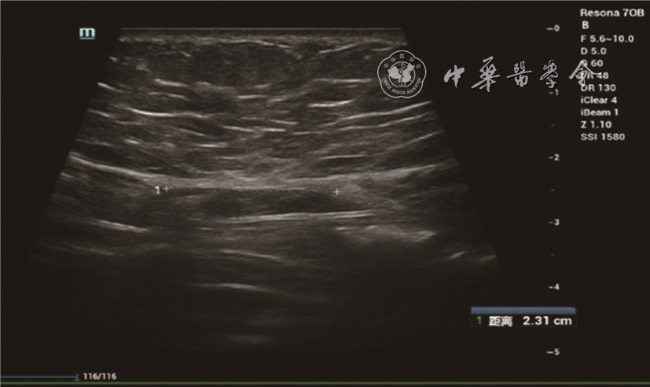

图2 35岁初产妇产后43 d,脐上5 cm水平双侧腹直肌间距为2.3 cm